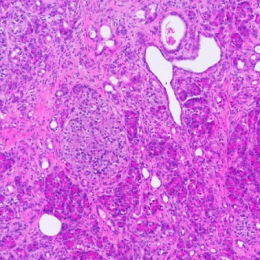

H&E | ANXA1 | ANXA10 | ANXA13 | |

|---|---|---|---|---|

Cancer tissue | ![]() | ![]() | ![]() | ![]() |

Unlock the essence of precision in cancer treatment with our PC organoids, mirroring the genetic markers of pancreatic cancer.

Performing WES analysis on 7pancreatic cancer (hPC) organoid samples, the top 25 gene mutations were observed to be noticeably present across the samples, indicating a high level of mutation.

According to these results, it appears that conducting experiments using the various types of pancreatic cancer samples we possess will likely yield results similar to those observed in actual human cases.